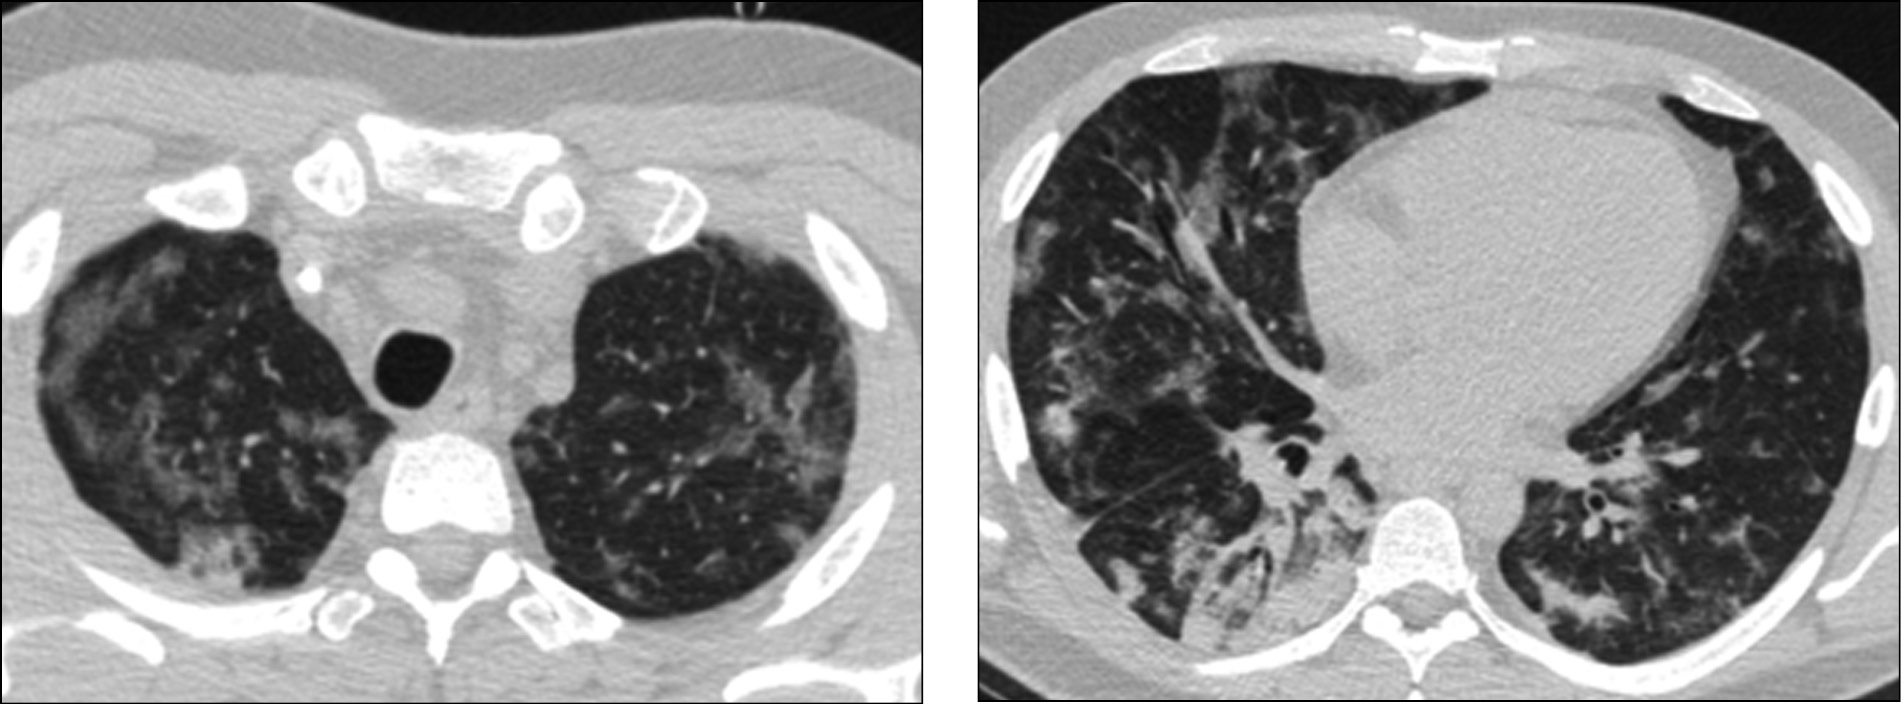

Антибактериальная терапия изменена на меропенем в дозе 2 г по 3 раза/сут. По данным микробиологического исследования выявлен Acinetobacter baumannii. В течение 3 дней лихорадка, лабораторные признаки воспаления и уровень прокальцитонина были нормализованы. Индекс PaO/FiO достиг 300, SpO2 98–99%. Оценка по SOFA 0 баллов. С 30.04.2020 пациент приступил к тренировкам самостоятельного дыхания, а со 02.05.2020 механическая вентиляция легких прекращена полностью, выполнена деканюляция трахеи. Респираторная терапия в объеме оксигенотерапии через назальные канюли 4 л/мин. Тест на COVID-19 (методом полимеразной цепной реакции) от 01.05.2020 положительный. КТ от 02.05.2020 с дальнейшей положительной динамикой (рис. 3).

Рис. 3. Компьютерная томография легких 02.05.2020: положительная динамика на фоне лечения